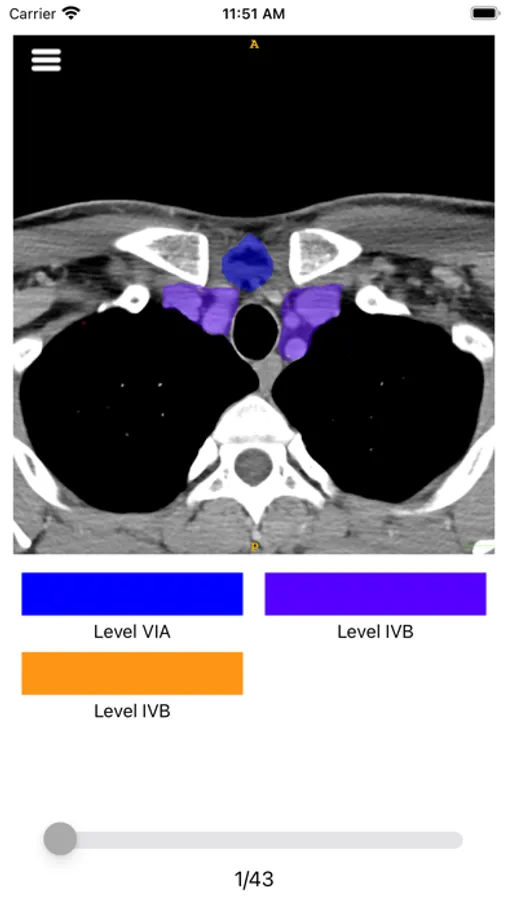

Neck lymph node map is an educational free app created for radiology residents and health care professionals practicing medical imaging. This robust app provides anatomical landmarks with an intuitive user interface for the description of neck lymph node levels on high-resolution axial CT soft tissue neck series using different color codes based on relevant cited literature. This app shows neck lymph node stations as visually well-delineated sections aiding in an easy understanding of the cervical lymph node levels, thereby contributing to more accurate diagnostic imaging interpretation at your fingertips on your mobile device.

Neck lymph node map Screenshots